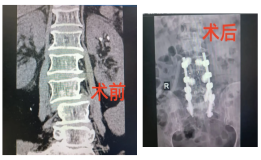

勇闯生命禁区,心脊双关创奇迹——我院疼痛脊柱科成功为77岁心脏瓣膜病患者完成高难度UBE镜下融合内固定手术

中西医协同破解老年脊柱侧弯难题,我院脊柱外科成功开展高难度开放融合手术